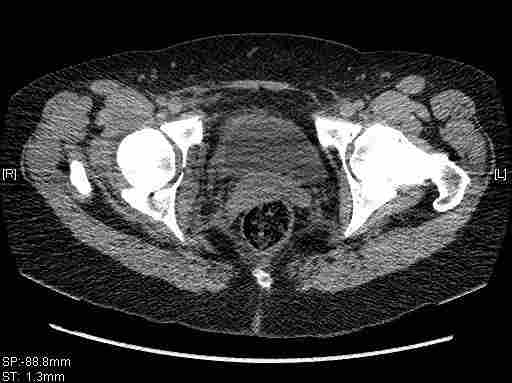

имеется передний подвывих, головка нагружаемой зоной будет "тереться" о край фрагмента, связанного с осевым скелетом.

вероятность быстрого прогрессирования коксартроза велика, хотя вряд ли кто-то укажет конкретные сроки. 1 год - 1,5 ?

Уважаемый Коваленко А.Н., снимки плохого качества и нет уверенности, что задняя колонна сломана (смещена). Если кт нет - везите больную в рентгенкабинет (палатником качественные снимки снимки не получатся) и сделайте обзорный снимок таза, Judet и может быть inlet, хуже вы ей не сделаете.

Вытяжение не поможет в любом случае, т.к. потянуть за одну переднюю колонну не получится. Есть вариант закрытого лечения, но для этого нужно наоборот сдавить крылья (скажем аппаратом), если больше переломов переднего полукольца нет, то передний подвывих уменьшится.

Приветствую,Антон.Рункова рядом нет,но после полученных данных КТ,обсуждали совместно.Итог обсуждения-развернутый ответ дать не получится,т.к.срезы выбраны не информативные.Если ориентироваться на данные 3D,то ,ИМХО,можно лечить на вытяжении.